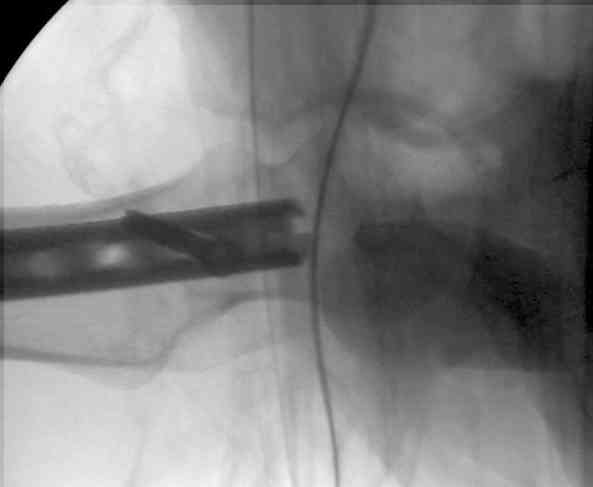

Если имеете доступ к trochanteric медуллярным штифтам TAN Smith Nephew или DePuy, где имеется offset на 8 градусов для удобства черезвертельного введения и профилактики нарушения кровеснабжения

головки (см. снимок) можно было применить штифт, в котором опороспособность достигается за счет блокирующих шурупов сверху и снизу.